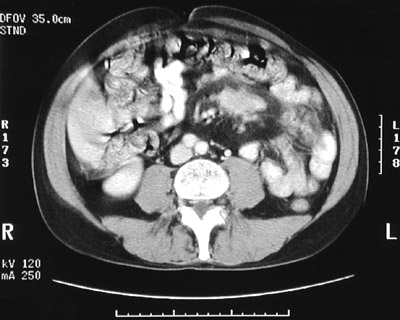

There is a mass composed of enlarged lymph nodes seen in this abdominal CT scan. In the view below, there is a central area of decreased intensity in the mass that corresponds with central caseous necrosis as a result of mycobacterial infection.